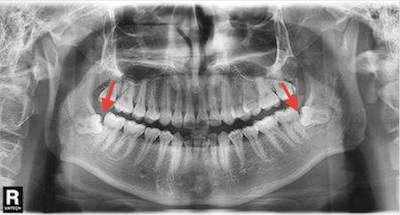

5/ 智齿萌出的方向不正常,也会造成食物易嵌塞在倾斜的空隙里。

- 智齿造成经常塞牙的,考虑拔除智齿。